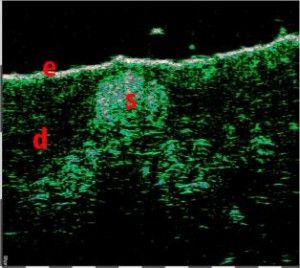

-Υπέρηχος Υψηλής Συχνότητας (HFUS) και Ιστολογία

-Διάγνωση μορφών ακμής

Εφαρμογές ογκολογίας